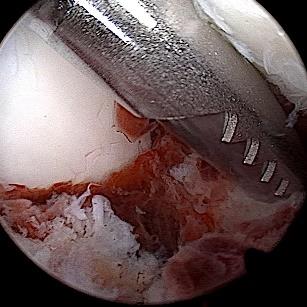

• 关节镜技术联合钉中钉系统全内修复跟骨关节内骨折的临床疗效观察

2026, 32(1):19-25. DOI: 10.12235/E20250392

摘要 (74) HTML (35) PDF 2.90 M (82) 评论 (0) 收藏

摘要:目的 探讨关节镜技术联合钉中钉系统全内修复跟骨关节内骨折的临床疗效。方法 回顾性分析2021年5月-2024年4月该院骨与关节康复科收治,并获得随访的31例闭合性跟骨关节内骨折患者的临床资料。均采取关节镜技术联合钉中钉系统全内修复手术治疗方案。术前及术后均行跟骨侧轴位X线片及足部CT检查,根据影像学结果对骨折类型进行分型,并评价术后骨折复位情况。比较手术前后跟骨高度、宽度、Bohler角和Gissane角。记录术前等待时间、手术时间、术中出血量、住院时间、术后疼痛视觉模拟评分法(VAS)评分等围手术期相关指标及术后并发症发生情况。采用美国足踝外科协会(AOFAS)评分和Maryland足部评分评估临床疗效。结果 术后影像学检查,可见跟骨术后关节面塌陷骨块复位;跟骨高度明显高于术前,跟骨宽度明显窄于术前,Bohler角较术前明显增大,Gissane角较术前明显缩小,差异均有统计学意义(P < 0.05)。术前等待时间为6(4,7)d,手术时间为(188.77±39.53)min,术中出血量为(59.03±23.00)mL,住院时间为(16.49±4.04)d,术后疼痛VAS评分为2(1,2)分,AOFAS评分为92(90,95)分,Maryland评分为92(90,95)分。结论 采用关节镜技术联合钉中钉系统全内修复跟骨骨折,具有可早期开展手术、创伤小、直视下复位、固定可靠和无切口相关并发症等优点,适用于Sanders Ⅱ型和Ⅲ型跟骨骨折。值得应用于临床。